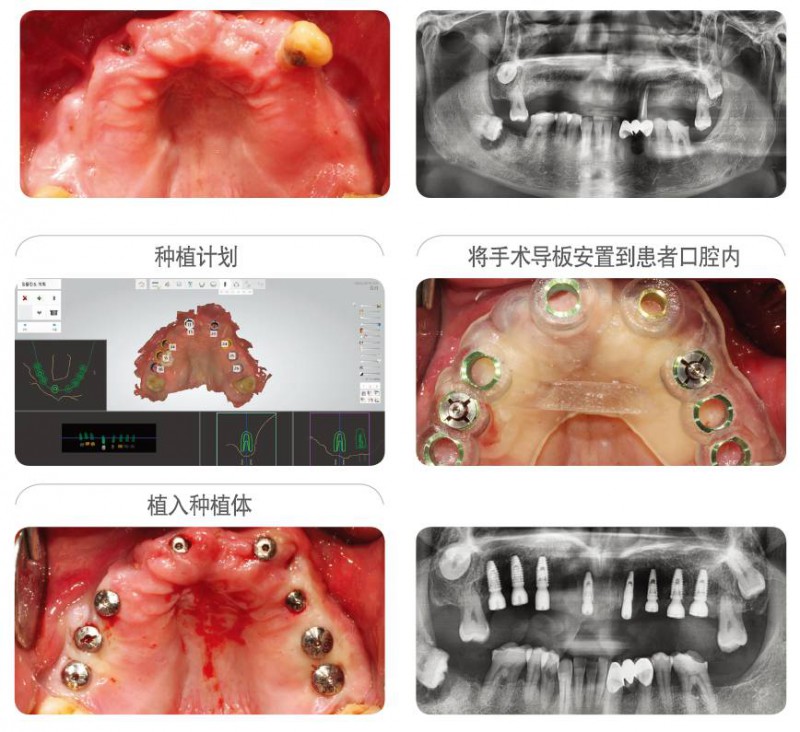

病例信息 : ST 牙科診所, 60s男性患者.

首次開展種植的牙科醫(yī)生為自己家人施術(shù)的案例.利用紐白特數(shù)字化手術(shù)導(dǎo)板簡單的植入8顆種植體,使得在顧問醫(yī)生的幫助下制定的治療計劃,完美的再現(xiàn)在患者口腔內(nèi)。